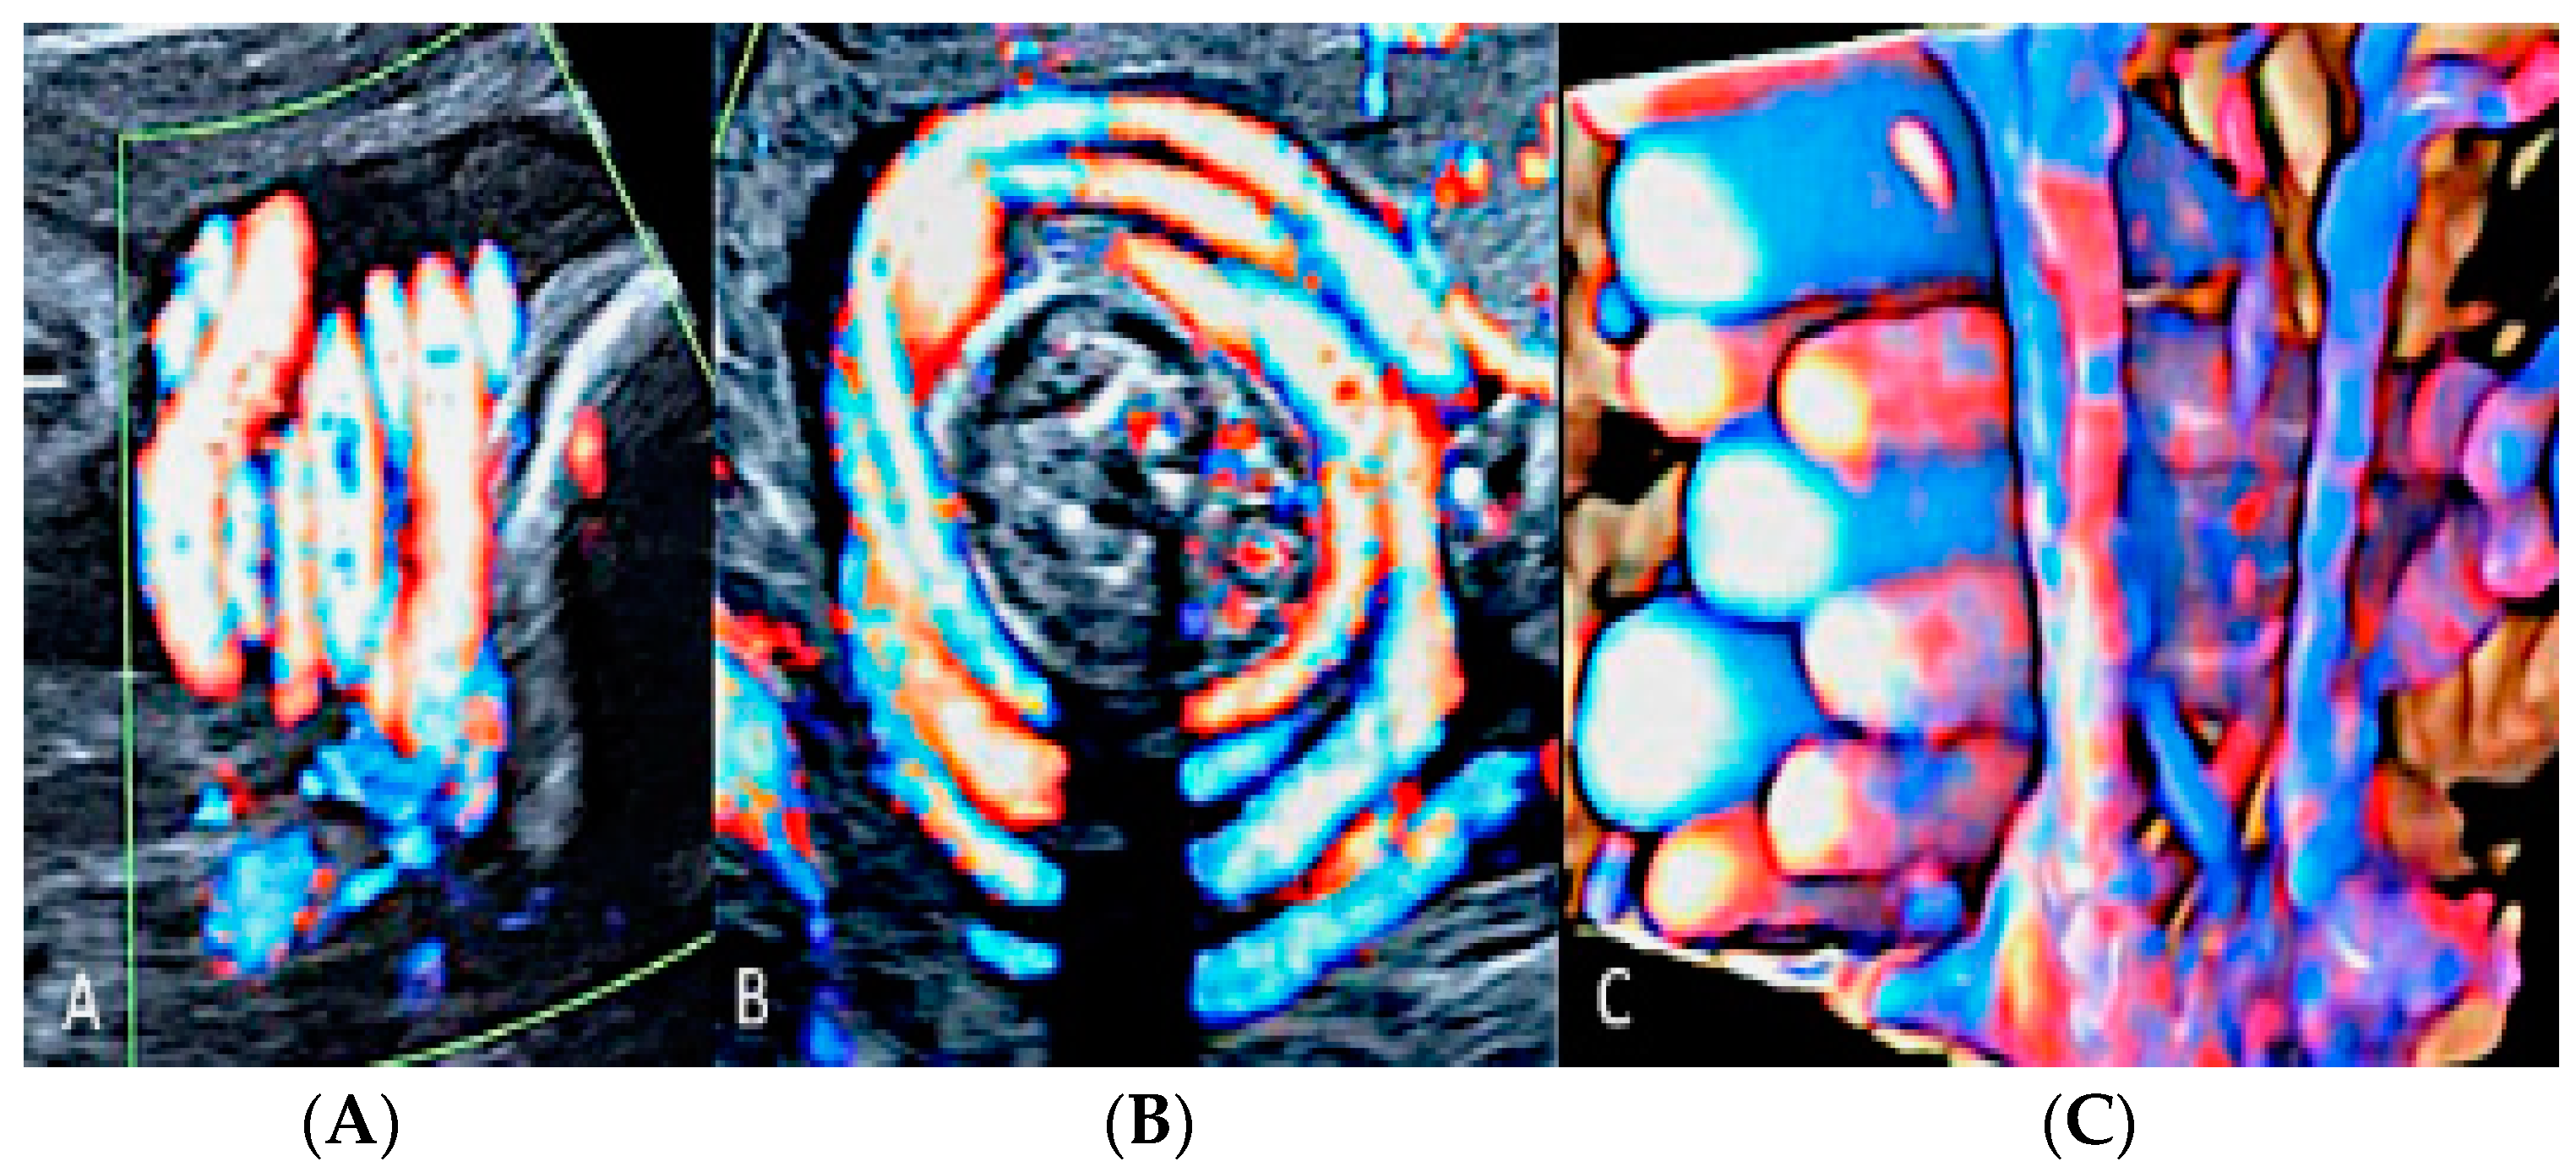

3.2.1. Nuchal Cords

- Hasegawa, J. Ultrasound Assessment of the Umbilical Cord. Donald Sch. J. Ultrasound Obs. Gynecol. 2014, 84, 382–390. [Google Scholar]

- Strong, T.H.; Jarles, D.L.; Vega, J.S.; Feldman, D.B. The umbilical coiling index. Am. J. Obstet. Gynecol. 1994, 170, 29–32. [Google Scholar] [PubMed]

- Mittal, A.; Nanda, S.; Sen, J. Antenatal umbilical coiling index as a predictor of perinatal outcome. Arch. Gynecol. Obstet. 2015, 291, 763–768. [Google Scholar]